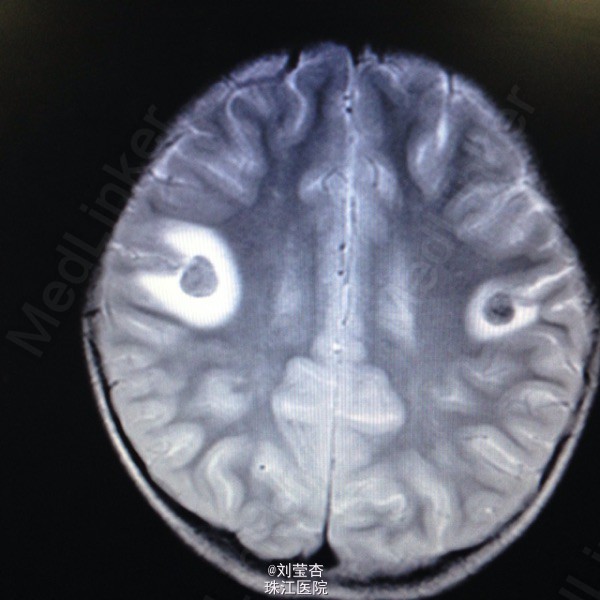

患儿女,3岁,因“咳嗽、流涕6天,发热5天,抽搐1次”入院。患儿接触家猫后出现流清涕,伴咳嗽,为间断单声咳,2天后出现发热,热峰39.5℃,予退热处理,患儿仍有反复发热,后患儿出现双眼向中上方凝视,双眼眼周肌肉抽动,伴口角流涎,无伴口周发绀、牙关紧闭,神志清楚,呼之可应,体温不详,四肢末梢温暖,四肢肌张力不高,持续约1分钟后可自行缓解。到当地医院就诊,查血常规:白细胞10.8G/L,中性粒细胞66.1%,淋巴细胞百分数27.1%,血红蛋白110g/L,血小板272 G/L,CRP4.2mg/L;胸片示支气管炎;头颅CT示右侧颞叶、双额叶多发散在脑出血。予吸氧、退热、抗感染、抗炎、补液、降颅压、止血等处理,患儿未再出现抽搐,患儿仍有反复发热,家属要求转我院进一步治疗。

查体:浅昏迷,反应一般,CRT2s,左侧耳后级颌下可触及3个肿大淋巴结,大小为0.5*0.5cm,质软,可活动,无压痛,与周围组织不粘连,双侧瞳孔等大不等圆,左侧瞳孔3mm,右侧瞳孔2.5mm,对光反射灵敏,口腔黏膜可见散在溃疡,咽部粘膜充血,双侧扁桃体Ⅰ度肿大,充血,未见黄白色脓点及分泌物,颈部稍抵抗,双肺呼吸音粗糙,可闻及大量痰鸣音,脑膜刺激症Kernig征可疑阳性,Brudzinski征可疑阳性。病毒八项:RUBE-IgG 26.8IU/Ml,CMV-IgG 117U/Ml,HSV-IgM 2.3S/CO,HSV-IgG 21.0S/CO,病毒两项:EB病毒DNA定量<5.00E+02(阳性)拷贝/mL,巨细胞病毒DNA定量9.65E+02(阳性)拷贝/mL;脑脊液常规:无色,透明,RBC 420M/L,WBC 40M/L,红细胞形态基本正常,潘氏试验(-);脑脊液单纯疱疹病毒DNA定量:单纯疱疹Ⅰ型DNA定量4.79+03(阳性)拷贝/mL,单纯疱疹Ⅱ型DNA定量低于检测下限拷贝/mL。

诊断:1.病毒性脑炎(单纯疱疹病毒感染)2.支气管肺炎。入院后予抗炎、抗病毒、抗惊厥、脱水、降颅压、促醒、输血浆,改善循环、雾化吸入、维持水电质平衡、营养支持等治疗。